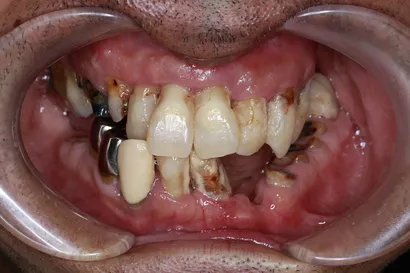

重度虫歯からの全顎インプラント治療

40代 男性

執刀医 Dr.大杉 治療内容 1回の手術でインプラントを埋め込み、即時の仮歯を装着して早期の機能回復を図りました。その後、噛み合わせを調整し、セラミックの製作を行いました。

上顎:ピンクポーセレンを用いたフルジルコニアインプラントブリッジ(All-on-4)

下顎:ピンクポーセレンを用いたフルジルコニアインプラントブリッジ(All-on-4)治療期間 1年 費用 上顎:330万 税抜

下顎:330万 税抜リスク 術後、硬い物を食べないでください。インプラントが骨に結合するまで2ヶ月かかります。この期間中に強い負荷をかけると、結合しないことがあります。 -